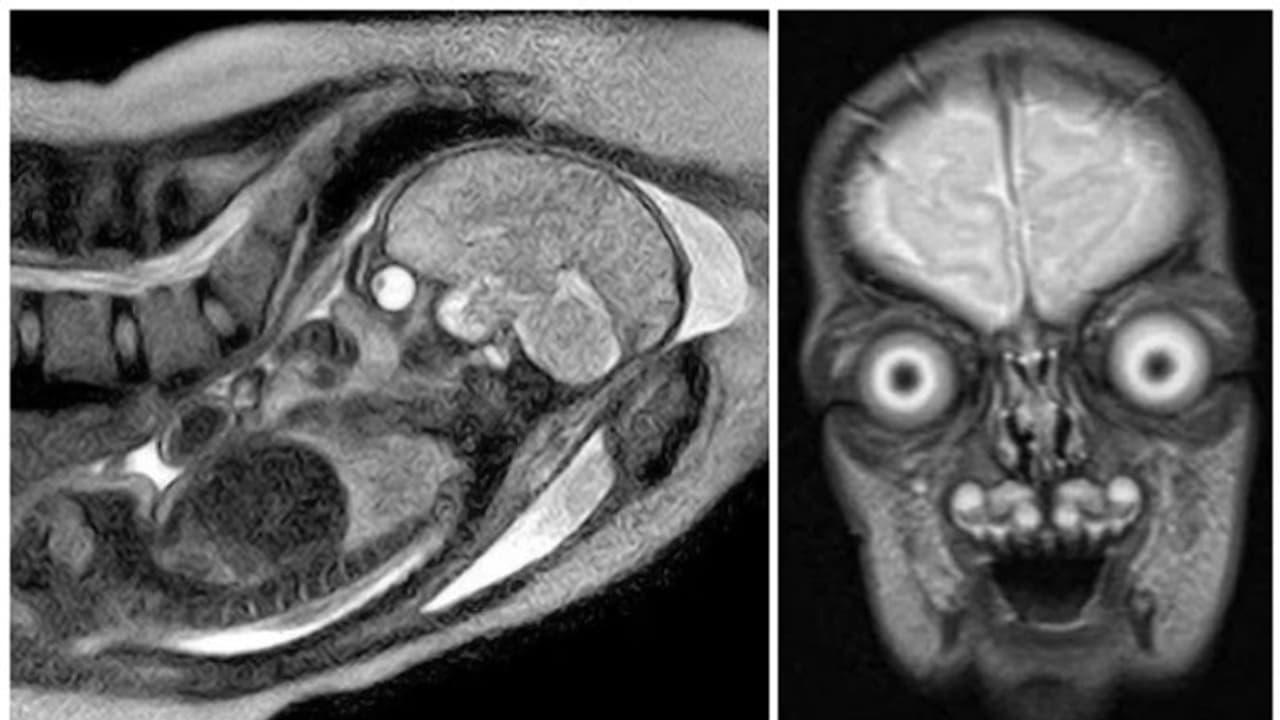

എംആര്ഐ സ്കാനിംഗ് ചെയ്താല് ഗര്ഭപിണ്ഡത്തിന്റെ തത് സമയത്തെ വളര്ച്ചയുടെ ചിത്രം ലഭിക്കുന്നു. കറുപ്പിലും വെളുപ്പിലുമുള്ള ചിത്രങ്ങളായിരിക്കും ഇത്തരം സ്കാനിംഗുകളില് ലഭിക്കുക. എന്നാല് ഇത്തരം ചിത്രങ്ങള് നമ്മുടെ ചിന്തയ്ക്കും അപ്പുറത്തുള്ള ഒരു കാഴ്ചയാകും സമ്മാനിക്കുക.

ഗര്ഭാശയത്തിന്റെ എംആര്ഐ സ്കാനിംഗുകള് അത്ര സാധാരണമല്ല. അവ അൾട്രാസൗണ്ട് സ്കാനിംഗിൽ നിന്നും വ്യത്യസ്തമാണ്. അതിനാല് തന്നെ അമ്മയ്ക്കോ ഗര്ഭസ്ഥ ശിശുവിനോ ആവശ്യമാണെങ്കില് മാത്രമേ എംആര്ഐ സ്കാനിംഗ് ചെയ്യുകയൊള്ളൂ. എന്നാല്, ഗര്ഭപിണ്ഡങ്ങളിലെ കഴുത്ത്, തൊറാസിക്, വയറ്., നട്ടെല്ല് എന്നിവയുടെ വൈകല്യങ്ങൾ നിർവചിക്കാനും കണ്ടെത്താനും അവയ്ക്ക് കഴിയുമെന്ന് ഗ്രേറ്റ് ഓർക്കണ്ട് സ്ട്രീറ്റ് ഹോസ്പിറ്റല് നിര്ദ്ദേശിക്കുന്നു. എംആര്ഐ സ്കാനിംഗ് ചെയ്താല് ഗര്ഭപിണ്ഡത്തിന്റെ തത് സമയത്തെ വളര്ച്ചയുടെ ചിത്രം ലഭിക്കുന്നു. കറുപ്പിലും വെളുപ്പിലുമുള്ള ചിത്രങ്ങളായിരിക്കും ഇത്തരം സ്കാനിംഗുകളില് ലഭിക്കുക. എന്നാല് ഇത്തരം ചിത്രങ്ങള് നമ്മുടെ ചിന്തയ്ക്കും അപ്പുറത്തുള്ള ഒരു കാഴ്ചയാകും സമ്മാനിക്കുക.

2021 ല് ഇത്തരത്തില് ഒരു ചിത്രം സാമൂഹിക മാധ്യമങ്ങളില് പങ്കുവയ്ക്കപ്പെട്ടിരുന്നു. സമാനമായ ചിത്രങ്ങള് കഴിഞ്ഞ ദിവസം സാമൂഹിക മാധ്യമങ്ങളില് വീണ്ടും വൈറലായി. ഈ ചിത്രങ്ങള്, ഗര്ഭപാത്രത്തിലുള്ള മനുഷ്യ ശിശുവിനെ കുറിച്ചുള്ള നമ്മുടെ ധാരണകളെ തകിടം മറിക്കുന്നവയാണ്. 2021-ൽ ഹാർവാർഡ് മെഡിക്കൽ സ്കൂളിന്റെ പിന്തുണയോടെ നടന്ന പ്രോജക്റ്റിന് പിന്നാലെയാണ് ഇത്തരം ചിത്രങ്ങള് സാമൂഹിക മാധ്യമങ്ങളില് പങ്കുവയ്ക്കപ്പെട്ടത്. ചിത്രങ്ങള് കണ്ട നെറ്റിസണ്സില് മിക്കവരും ചിത്രങ്ങള് കണ്ടപ്പോള് തങ്ങള്ക്കുണ്ടായ ആശങ്കകള് പങ്കുവച്ചു. ചിത്രങ്ങള് കണ്ടാല് പിശാചുക്കളാണ് ജനിക്കാന് പോകുന്നതെന്ന് ആളുകള് ഭയക്കുമെന്നായിരുന്നു മിക്കവരും കുറിച്ചത്. ചിത്രങ്ങള് കാഴ്ചക്കാരില് പേടിസ്വപ്നങ്ങള് ഉണ്ടാക്കുമെന്ന് എഴുതിയവരും കുറവല്ല. ചിലര് അത്തരം ചില രൂപങ്ങള് കോമിക്ക് പുസ്തകങ്ങളില് കണ്ടിട്ടുണ്ടെന്ന് രേഖപ്പെടുത്തി.

റെഡ്ഡിറ്റ് എന്ന സാമൂഹിക മാധ്യമത്തില് ഈ ചിത്രങ്ങള് പങ്കുവയ്ക്കപ്പെട്ടപ്പോള് ഇത് ഭൂമിക്ക് പുറത്ത് നിന്നുള്ള ജീവികളാണെന്നായിരുന്നു ചിലര് കുറിപ്പെഴുതിയത്. ചിത്രങ്ങള് ടിം ബർട്ടണിന്റെ അന്യഗ്രഹ ജീവികളെക്കുറിച്ചുള്ള സിനിമകളില് നിന്നുള്ളവയാണെന്നായിരുന്നു ചിലര് എഴുതിയത്. മറ്റ് ചിലര് സാത്താന്റെ സന്തതികളെന്ന് കുറിച്ചു. ചിത്രങ്ങള് വ്യാപകമായി പ്രചരിപ്പിക്കപ്പെട്ടതോടെ Snopes എന്ന ഫാക്റ്റ് ചെക്ക് വെബ്സൈറ്റ് അവ യഥാര്ത്ഥ ചിത്രങ്ങളാണെന്ന് കണ്ടെത്തി റിപ്പോര്ട്ട് ചെയ്തു. പ്രായവുമായി ബന്ധപ്പെട്ട മസ്തിഷ്ക മാറ്റങ്ങൾ പഠിക്കാൻ എംആർഐ സാങ്കേതികവിദ്യ ഉപയോഗിക്കുന്നുവെന്ന് വിസ്കോൺസിൻ സർവകലാശാലയിലെ ഗവേഷകര് അറിയിച്ചതായും അവര് റിപ്പോര്ട്ട് ചെയ്തു. ട്വീറ്റിലെ രണ്ട് ചിത്രങ്ങള് നേരത്തെ ഹാര്വാര്ഡ് സര്വകലാശാല ഗവേഷകര് പങ്കുവച്ചതായും വെബ്സൈറ്റ് റിപ്പോര്ട്ട് ചെയ്തു.